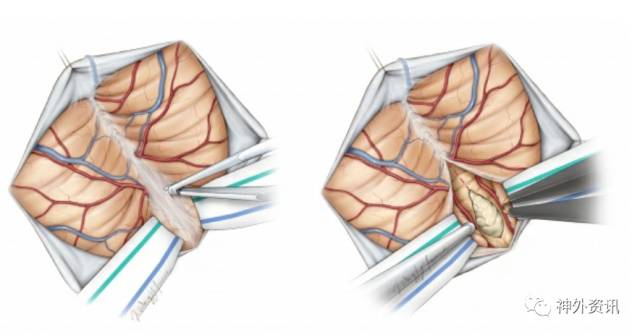

图10. 打开覆盖在小脑延髓池上的蛛网膜来释放脑脊液,从而减轻脑部受压。根据实际病变,用蛛网膜刀和纤维剪解剖中线的蛛网膜(左图)。经小脑蚓或膜髓帆入路更容易到达第四脑室病变(右图)(该图根据Tew,van Loveren和 Keller的图片重新绘制 )。